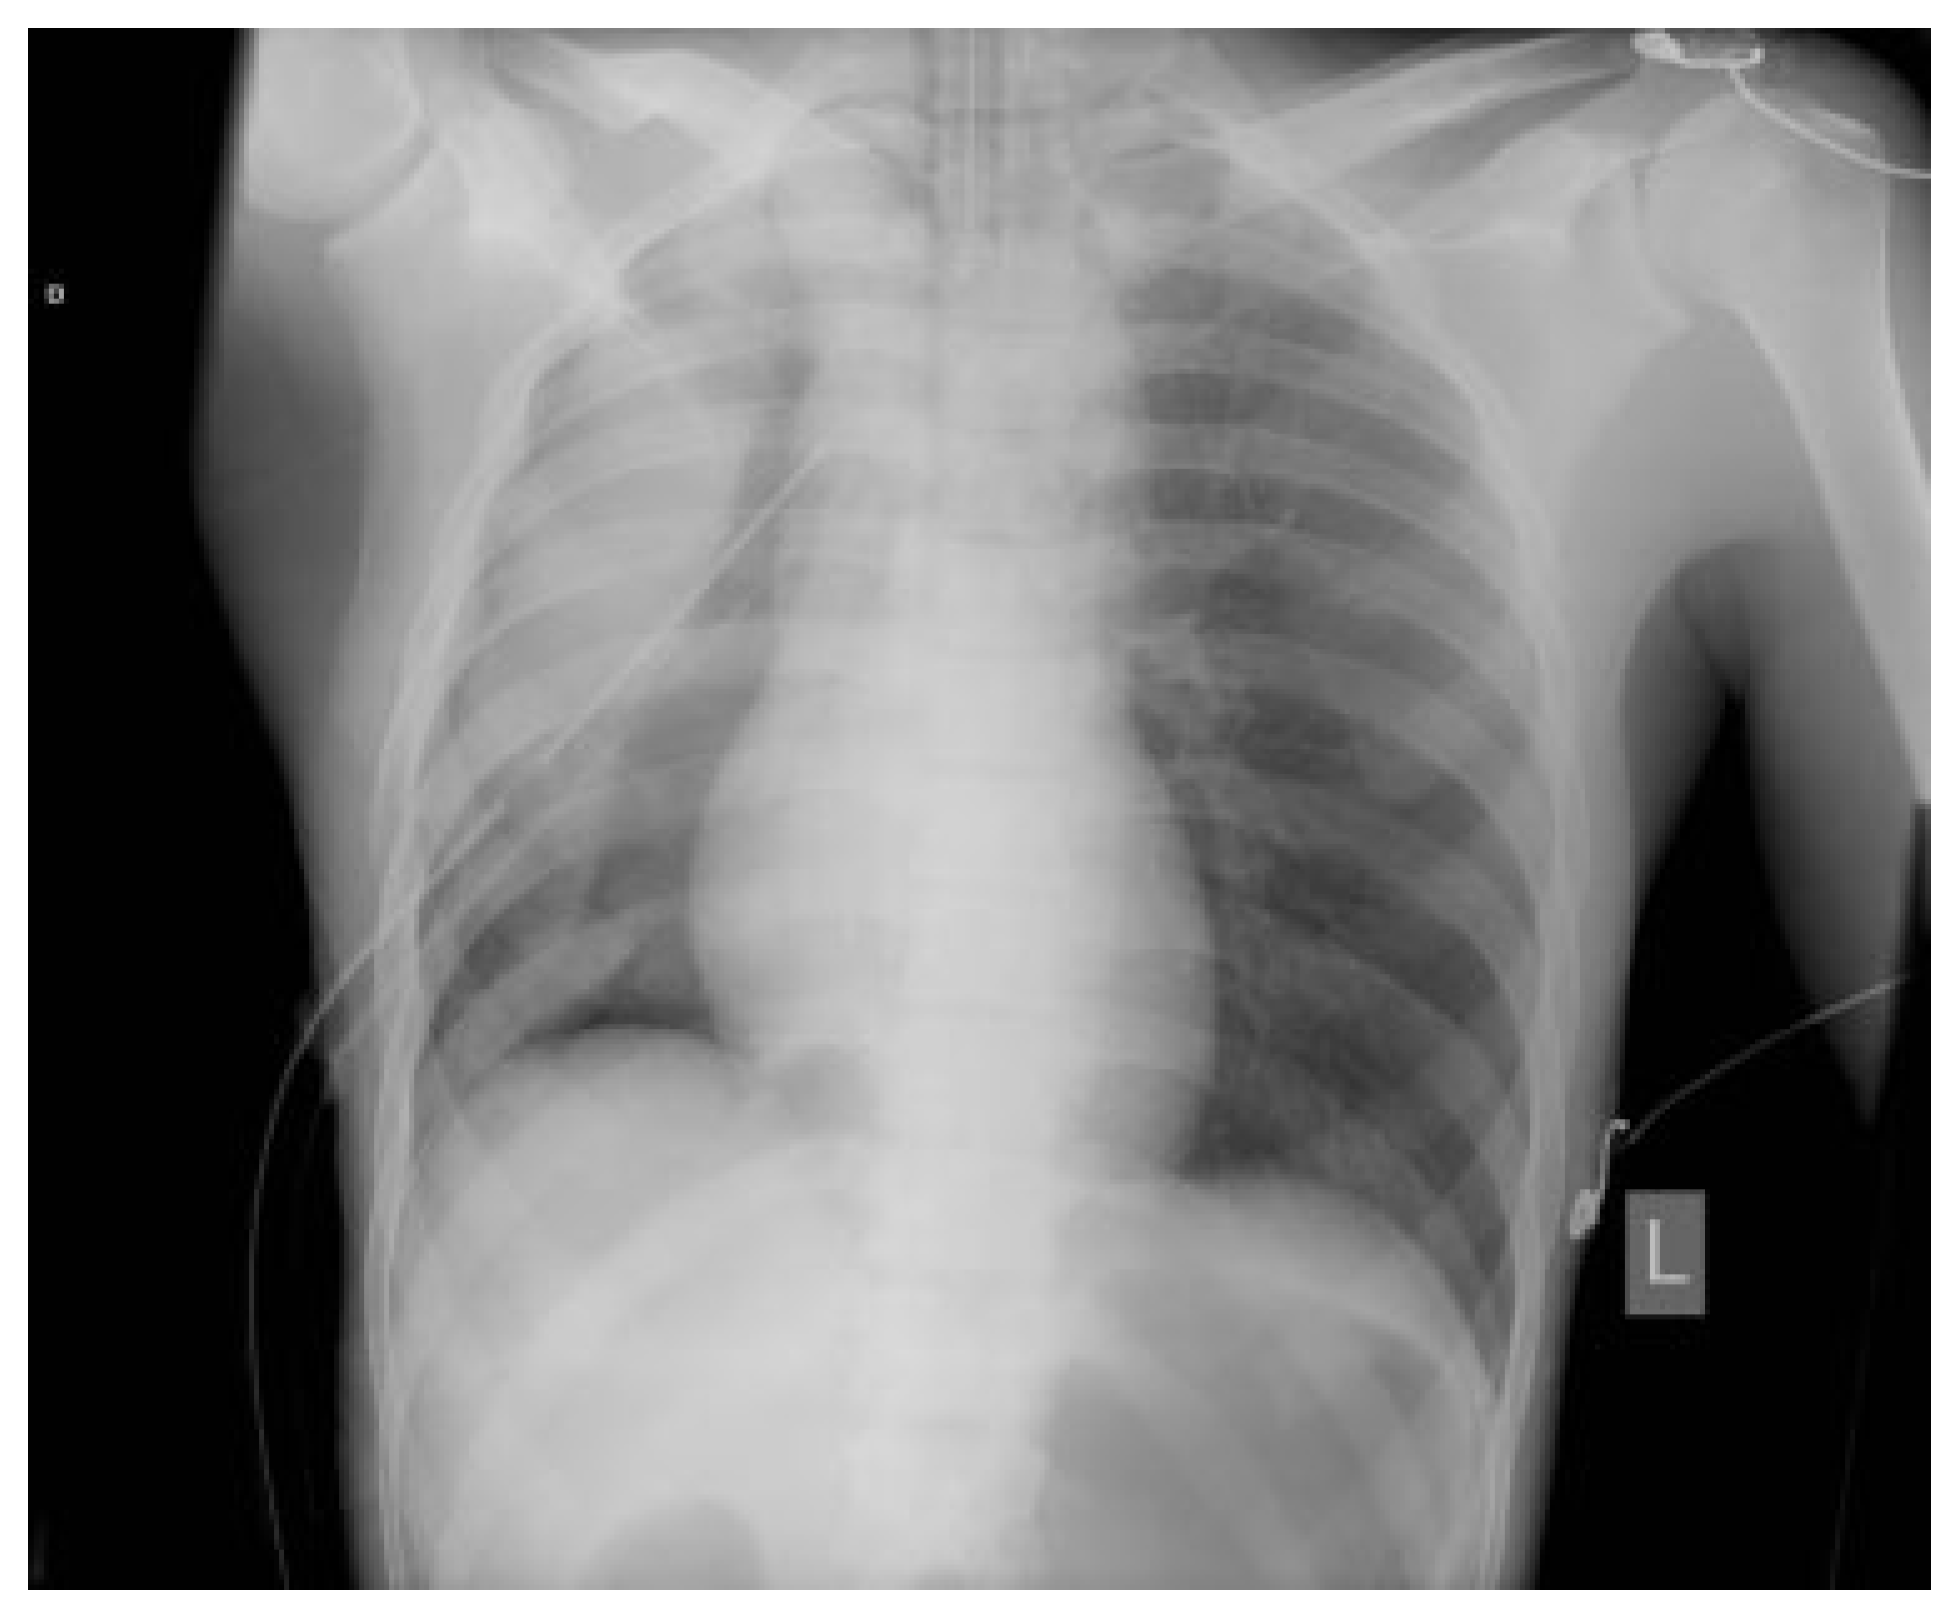

Anesthetic Complication During Maxillofacial Trauma Surgery: A Case Report of Intraoperative Tension Pneumothorax

Case Report